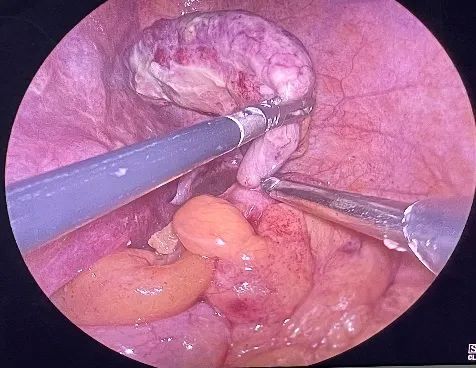

其中一位因诊断未明,选择保守治疗十余天,确诊时阑尾周围已形成脓肿,病情复杂。孕晚期子宫巨大,不仅遮挡了手术视野,更让腹腔镜操作如履薄冰——既要精准切除病灶,又要避免触碰子宫、确保胎儿安全。

面对家属的焦灼目光与孕妇的忐忑不安,医院迅速集结产科、普外科、麻醉科、手术室、ICU等多学科团队,反复论证手术方案,最终由肿瘤外科主任时红光主刀,成功实施高难度腹腔镜微创手术。术中克服了子宫压迫、脓肿粘连等重重挑战,术后孕妇顺利康复、胎儿平安,打赢了这场“生命保卫战”。